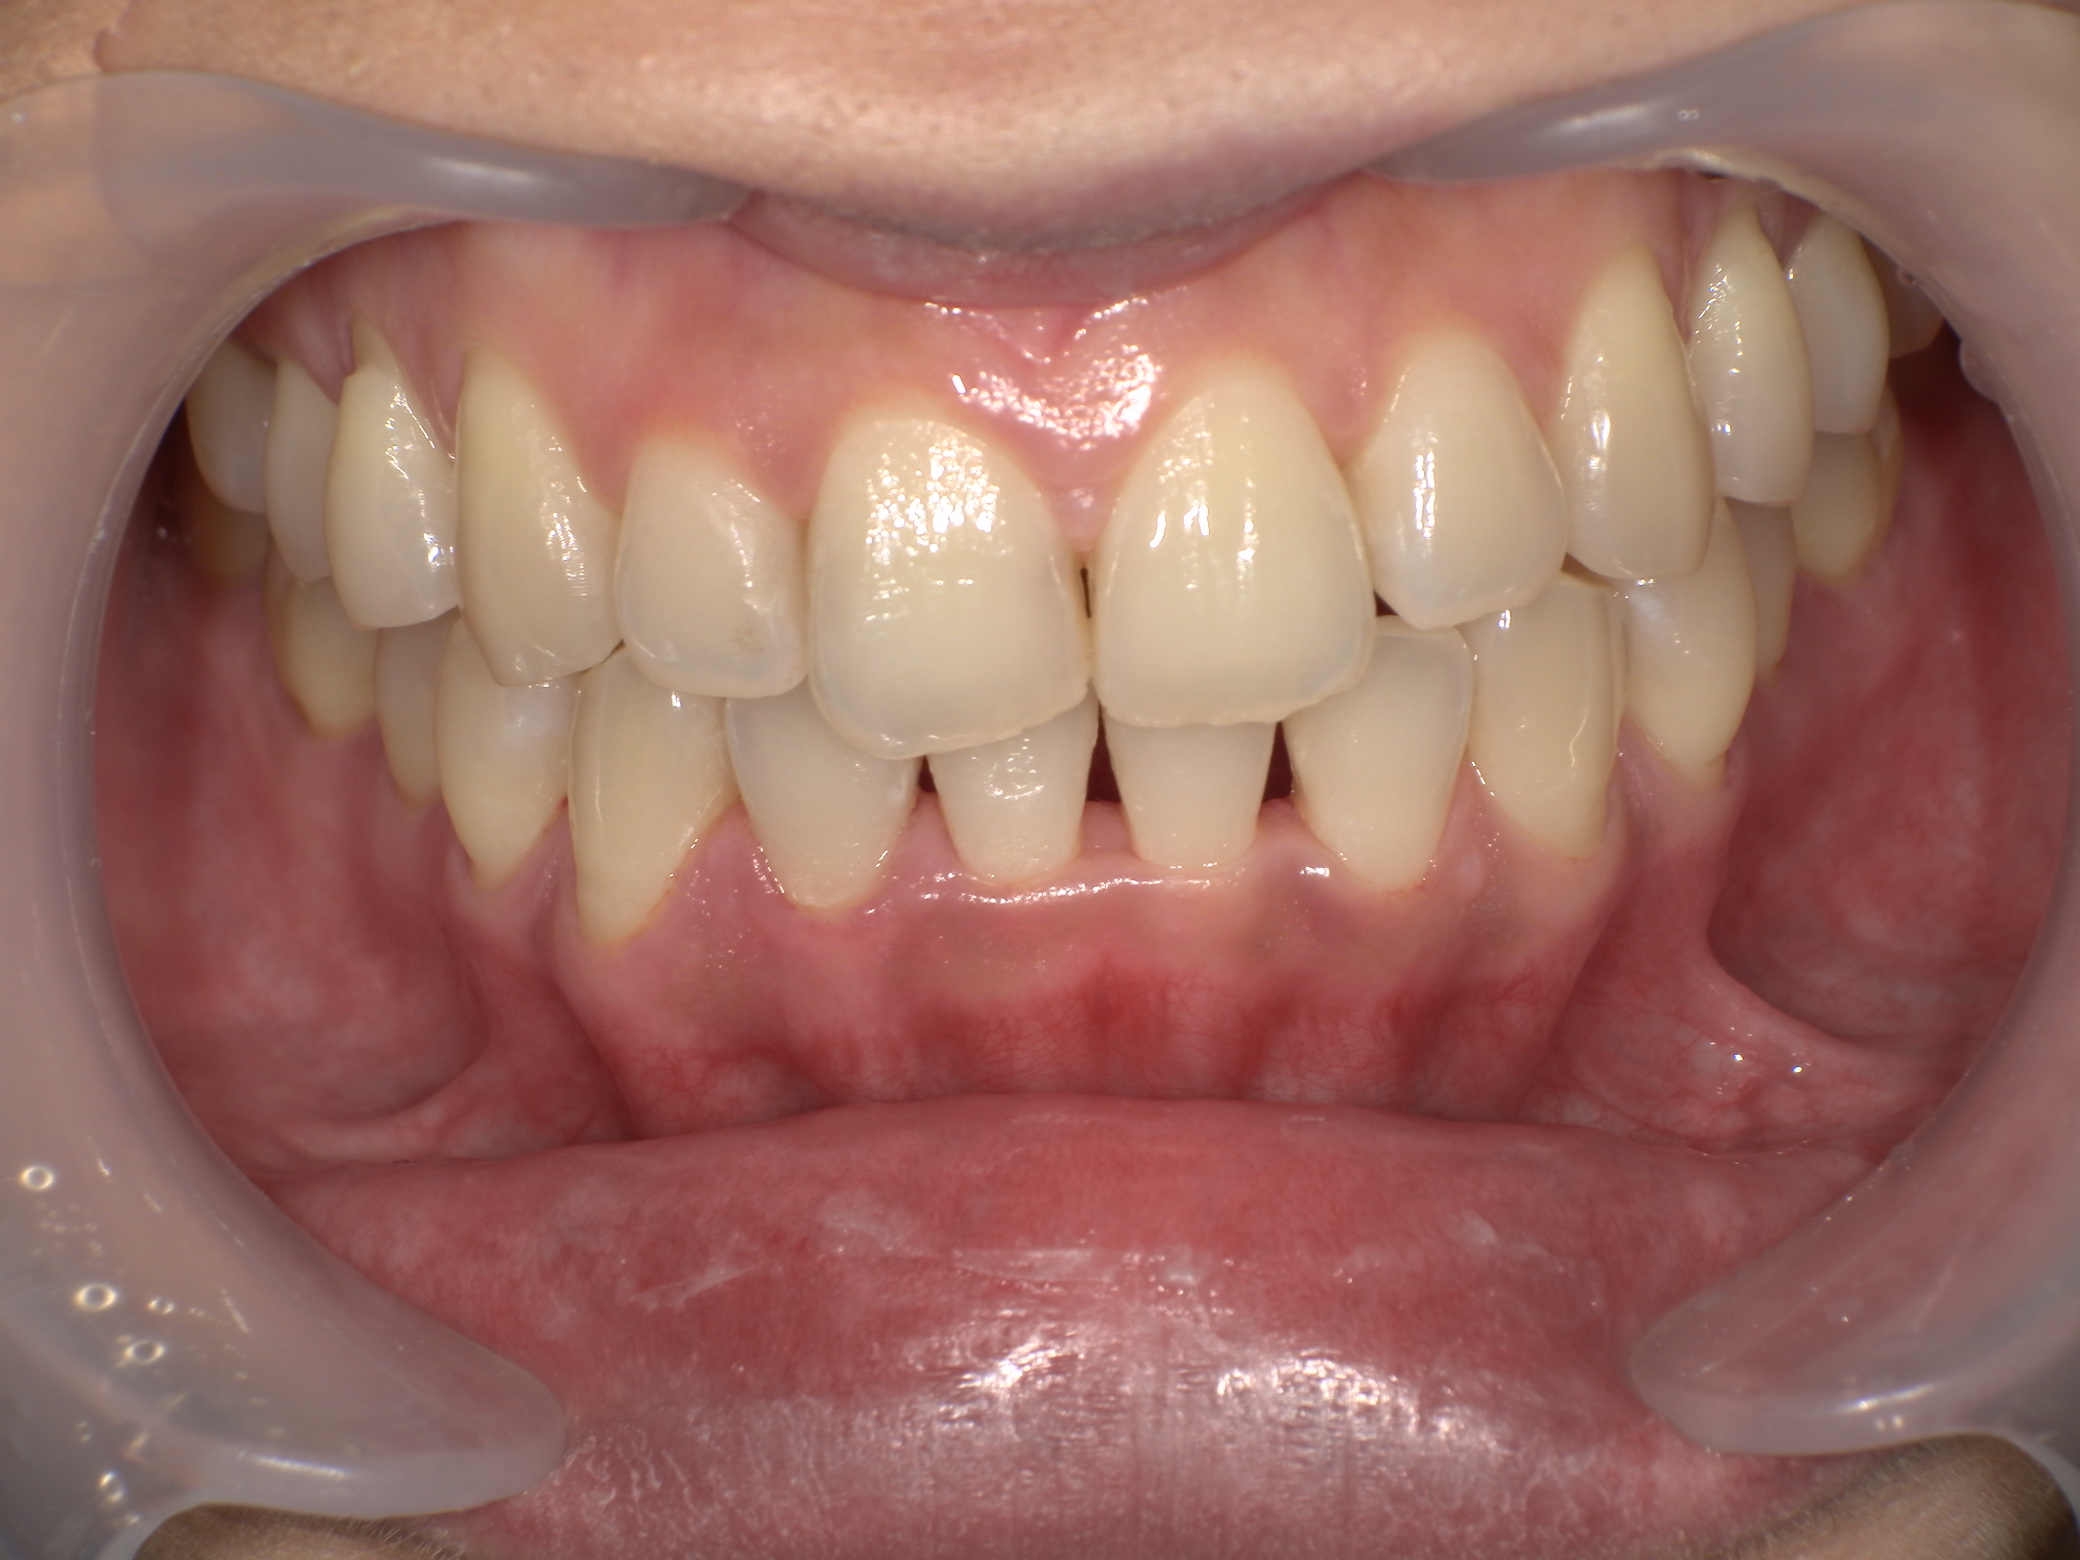

インビザライン症例|八重歯が気になっていて、マウスピース矯正の話を聞きたい

2026/02/28 成人矯正